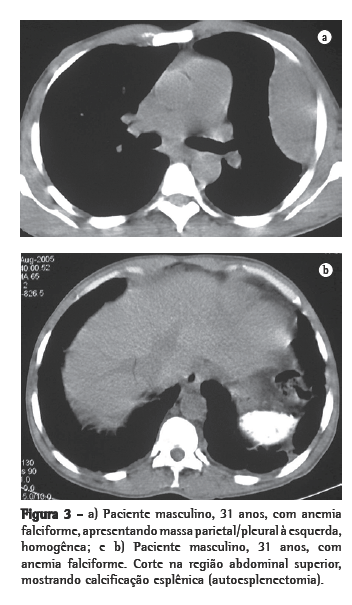

Dos seis pacientes, quatro apresentaram massas paravertebrais inferiores. Em três, elas eram bilaterais e relativamente simétricas, e em um era unilateral, à direita. Quanto ao conteúdo das massas, em três pacientes havia presença de tecido adiposo, sendo que em um desses o material gorduroso era bastante significativo. Em um paciente, as massas eram homogêneas, com densidade de partes moles (Figuras 1a e b, 2a e b).

Através da TC, podem ser observadas massas com densidade de partes moles, em sua maioria homogêneas, com características semelhantes às descritas na radiologia convencional,(1,2,5,6) que podem ou não ser realçadas após a administração do meio de contraste.(4,10) Este método de imagem é importante para analisar a estrutura interna das lesões, particularmente quando ricas em gordura,(5) para avaliar a presença de outras massas paracostais e para detectar alterações ósseas associadas a certas doenças hematológicas, como a talassemia e a anemia falciforme.(6) Nos casos relacionados a talassemia, anemia falciforme ou metaplasia mielóide, pode ocorrer um alargamento das cavidades medulares das costelas.(5)

As lesões ativas e recentes têm rica vascularização, enquanto que as antigas e inativas têm mais tecido gorduroso e deposição de ferro. Entre os dois extremos, existem várias combinações de achados, refletindo os diferentes estágios de evolução do foco hematopoiético. Os achados na TC e na RM de alguma forma traduzem essas diferenças histológicas. Lesões recentes e ativas têm densidade de partes moles na TC e intensidade de sinal intermediária na RM, tanto em T1 como em T2. Após a administração do meio de contraste, geralmente ocorre algum grau de impregnação nas lesões ativas. Lesões antigas e inativas podem mostrar aumento de densidade na TC, por impregnação pelo ferro, ou densidades negativas, pela infiltração gordurosa. Na RM, essas lesões podem mostrar alta intensidade de sinal tanto em T1 como em T2, pela infiltração gordurosa, ou baixa intensidade de sinal em ambas as ponderações, pela deposição de ferro.(4,8,12)